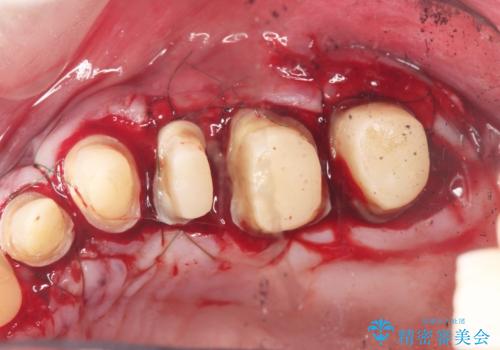

- 「虫歯が多発し、治療が終わらない。歯も無くなったし今後悪くならないような治療をしたい。」と精密治療を希望され来院されました。

虫歯の徹底的な除去やセラミック補綴、精密根管治療、歯周外科を行うことで、治療後に歯磨きがしやすく、かみやすい機能的な仕上がりへと導きます。

- 63.8万円(ジルコニアクラウン×4・仮歯×4・歯周外科) (上顎左側臼歯4本分の費用)費用は治療当時の料金となります

歯周外科手術をおこなったことでフェルールも獲得でき、破折リスクをより抑えることにも成功しています。